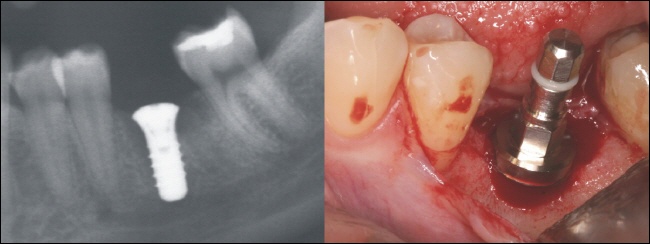

Ausgangssituation

Ein Zahn ist durch eine tiefe Karies verloren gegangen. Die Nachbarzähne sind nahezu unversehrt, nur der letzte Zahn hat eine kleine Füllung (weiß im Röntgenbild). Um weitere Folgeschäden zu vermeiden, entschied sich die Patientin für ein Zahnimplantat.

Implantation

Drei Monate nach der Zahnentfernung wurde in einem kleinen Eingriff ein Zahnimplantat in die Lücke gesetzt. Auf dem Röntgenbild links sieht man das Schraubenimplantat (weiß) und rechts das Zahnimplantat im Mund direkt nach dem Einsetzen. Der Einbringpfosten ist noch auf dem Implantat zu erkennen. Dieser wird abgeschraubt und auf das Implantat für die Einheilzeit eine flache Verschlusskappe aufgeschraubt.